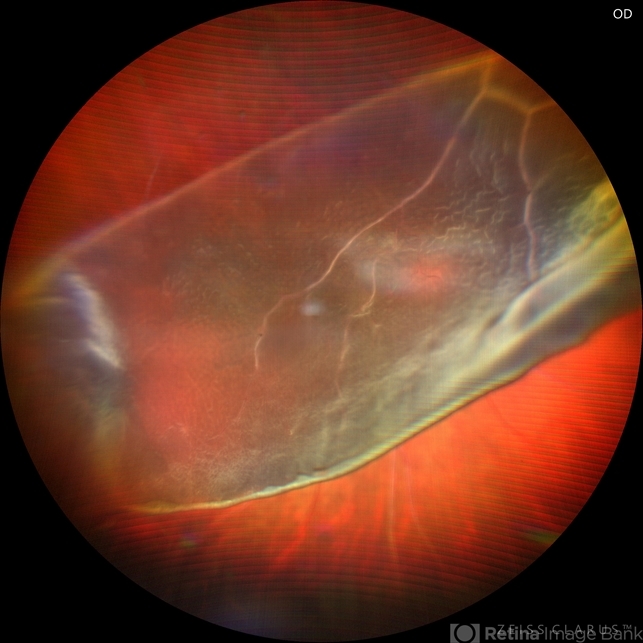

- Chloroquine maculopathy

- giant retinal tear, Retina detachment

- A complex case of retina detachment due to giant retinal tear